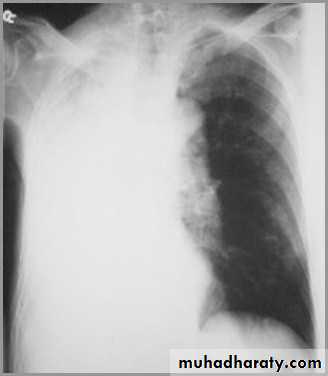

Differentiating the Causes of an Opacified Hemithorax

Atelectasis of an entire lungA large pleural effusion

Atelectasis of the Lung

There is a shift of heart and hemidiaphragm toward side of opacification (toward side of volume loss)Pleural Effusion